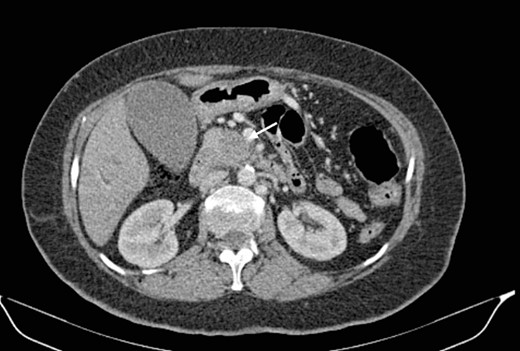

Mr. A. is a 65-year-old hypertensive patient presenting with acute epigastric pain associated with abdominal bloating. Biological settings showed amylasemia at 450 IU/L and lipasemia at 525 IU/L. Abdominal CT scan revealed heterogenous poorly defined mass in the pancreatic head with low enhancement (Figs 1 and 2). The CA 19–9 assay was 280 IU/L. Cephalic duodenopancreatectomy was performed. Histological examination of the operative specimen revealed a solid, trabecular, undifferentiated carcinomatous process (Fig. 3) expressing markers (CK(AE1-AE3) and p40) (Fig. 4), confirming the diagnosis of primary squamous cell carcinoma of the pancreas. The extension study showed no secondary localization.

Parenchymal atrophic changes and main pancreatic duct dilatation distal to the mass (blue arrow). Extra and intrahepatic bile ducts are dilated (red arrow).